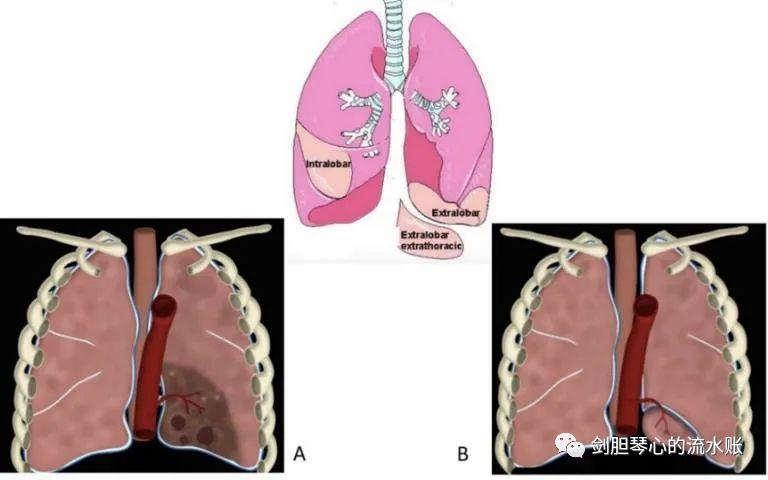

肺隔离症是一种先天性肺发育畸形,由异常的体循环动脉供应的无功能的肺组织所形成的囊性肿块,且不与气管支气管树相连。发病率为0.15-1.8%,是第二常见的先天性肺部异常。根据发病部位分为两型:

1, 肺内型隔离症

又称叶内型,较为常见, 局限于正常的肺实质内 。男女发病率大致相当,98%出现在 肺下叶 。 有症状 ,多为反复的肺部感染,罕见者会出现血气胸、咯血、充血型心衰等。

2, 肺外型隔离症

又称叶外型,相对不常见,主要发生在 内脏胸膜外的肺组织 。男女发病率约为4:3,多数无症状。大多数肺外型隔离症位于肺下叶和膈肌之间;但事实上可能出现在胸腔的任何部位,部分或全部出现在横膈膜内。横膈膜下方约占10-15%,,前纵隔占6%,后纵隔占15%。腹腔内占8%, 这部分需要与腹腔脏器的囊性占位性病变进行鉴别。